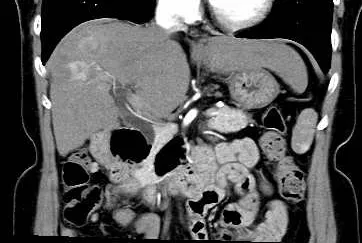

肝臓造影CT検査画像 肝臓造影CT検査画像

肝臓造影CT検査画像(大腸がん肝臓転移)